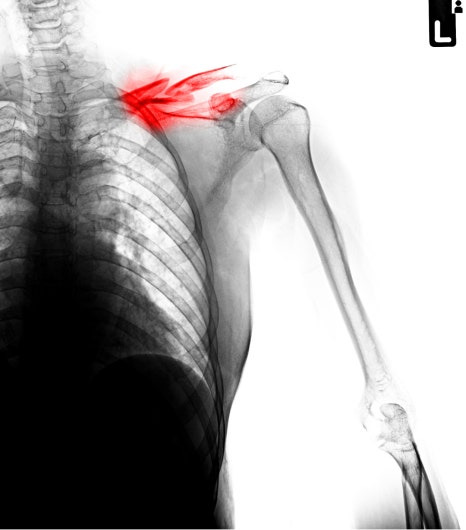

석회성건염은 어깨 힘줄 그 중에서도 주로 회전근개 부위에 칼슘 성분의 석회가 쌓이면서 염증 반응과 통증을 함께 유발하는 상태를 말합니다. 겉으로 보이는 상처나 붓기가 뚜렷하지 않아 처음에는 근육통이나 담 결림 정도로 오해되기 쉽지만 어깨 내부에서는 전혀 다른 변화가 진행되고 있는 경우가 많습니다.

이 질환의 가장 큰 특징은 통증의 원인이 사용량보다 석회의 존재와 움직임에 있다는 점입니다. 즉 어깨를 많이 쓰지 않았는데도 어느 날 갑자기 통증이 심해질 수 있다는 뜻이죠.